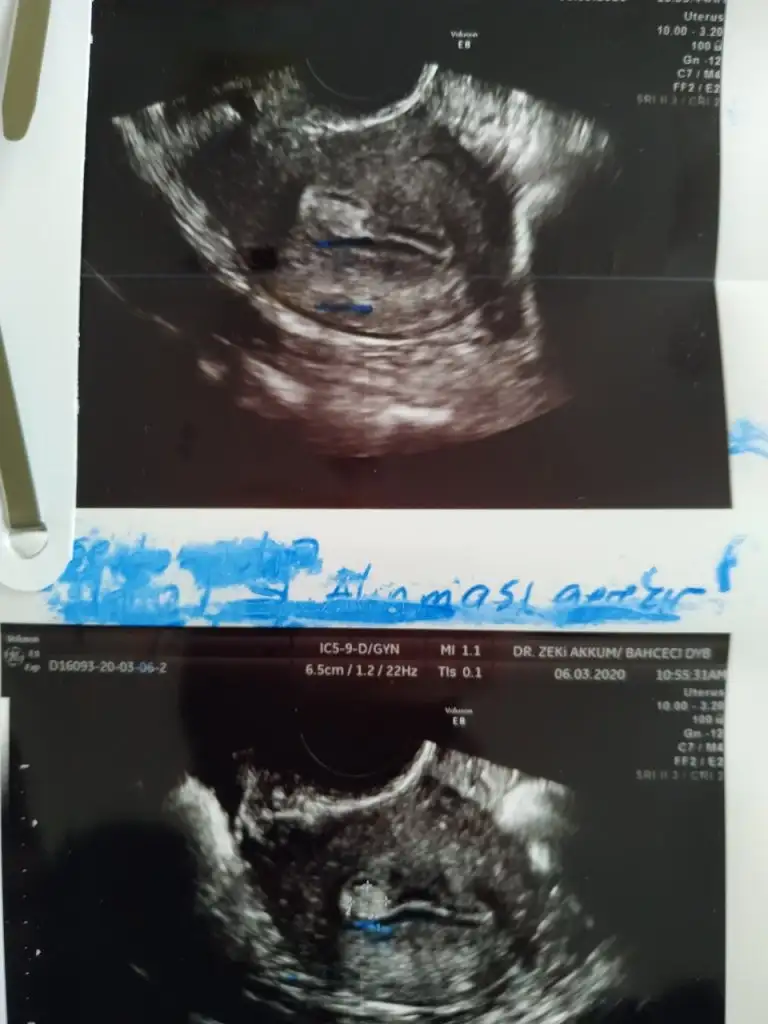

kızlar moralim bozuk tüp bebek tedavimde ilaçları kullanmaya başladım yumurta boyutunu kontrol amaçlı gittiğimizde doktorum rahmin içinde polip benzeri bi şey gördü görüntünün yanıltıcı olabileceğini ve emin olmak için yumurta toplama işleminde histereskopi yapacağını söyledi benimle aynı durumu yaşayan kızlar var mı bilgilerini paylaşırsa sevinirim

• polip.webp

polip.webp